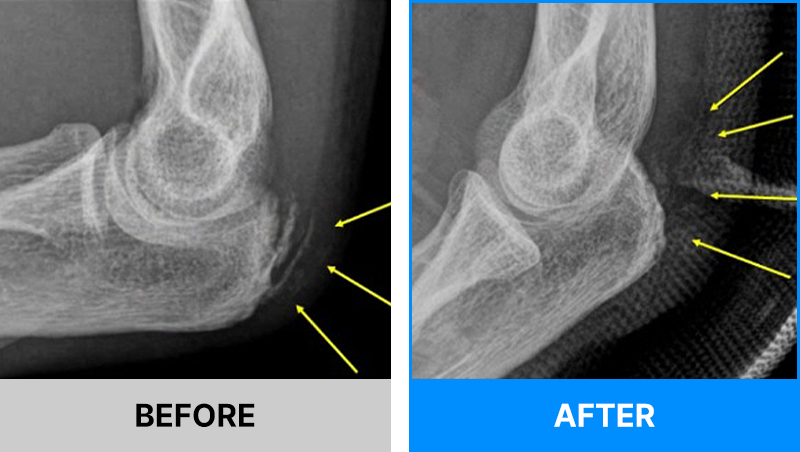

왜 당일 입퇴원 수술일까요?

오래 입원할 필요가 없기 때문입니다.

서울거탑정형외과에서는 전신마취, 척추마취가 아닌

국소부분마취(신경차단) 및 수면 마취를 통해 수술을 시행합니다.

수술 가능 여부 확인은 대표원장과의 진료가 필요합니다.